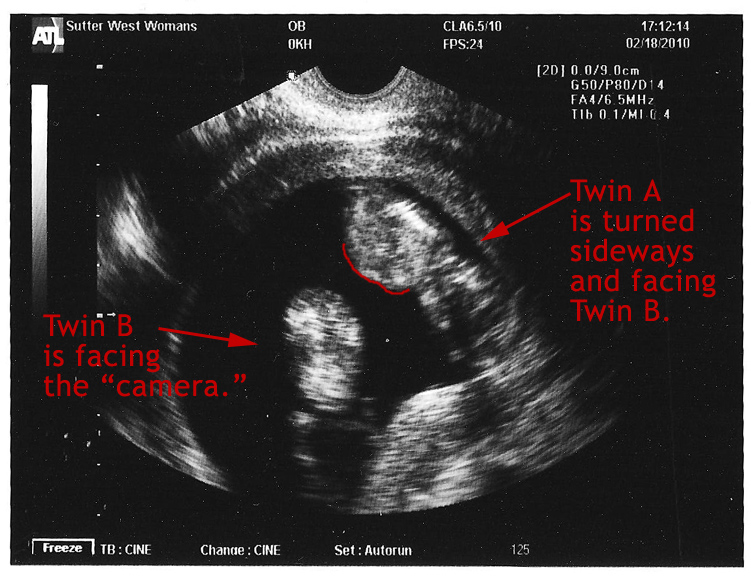

During a brief exam I was squeezed and prodded and pronounced healthy. Then, the nurse practitioner gave me 2 options: she could listen and try to distinguish the two heartbeats or we could go get a quick ultrasound to see how the tykes were doing. I wavered briefly because I felt bad that Puck was not here to share in the new ultrasound but my desire to see the twins won out. She whisked me across the hall and in seconds our twins were up on the screen together. The amazing little duo were more active than I had seen them before with their arms waving and their legs kicking. It was quite a sight to see.